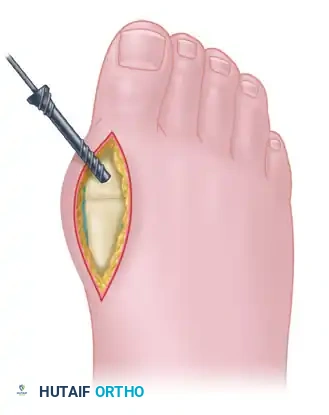

Make a dorsal longitudinal incision centered over the first MTP joint. The incision should be placed just medial to the extensor hallucis longus (EHL) tendon to avoid tendon irritation and bowstringing. Begin the incision just proximal to the interphalangeal joint and extend it proximally to approximately 3 cm proximal to the MTP joint.

Carefully dissect through the subcutaneous tissues, taking meticulous care to identify and protect the dorsomedial branch of the superficial peroneal nerve.

2. Capsulotomy and Joint Preparation

Open the joint capsule in line with the skin incision. Perform a thorough synovectomy, removing any hypertrophic synovium and dorsal osteophytes that may impede visualization. Release the joint capsule medially and laterally on both the phalangeal and metatarsal sides. This aggressive soft-tissue release is critical to expose the articular surfaces sufficiently and to allow for at least 3 to 5 mm of bony resection without tension.

Displace the proximal phalanx plantarly to fully expose the metatarsal head.

3. First MTP Arthrodesis via Medial Approach

Approach the first MTP joint through a separate direct medial incision. Carry the incision straight down to the bone, staying directly in the midline of the proximal phalanx, the metatarsal head, and the distal half of the first metatarsal shaft. Raise full-thickness dorsal and plantar flaps at the subperiosteal bone level, rather than extracapsularly, to preserve the vascular supply to the skin edges.

Resect the medial eminence (bunion) flush with the metatarsal shaft.